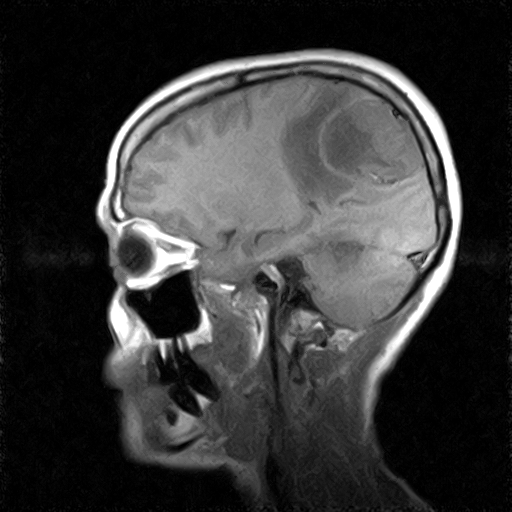

• Resonancia PATOLÓGICA DE CRANEO - MENINGIOMA -  SAG T1

• Resonancia PATOLÓGICA DE CRANEO - MENINGIOMA -  SAG T2